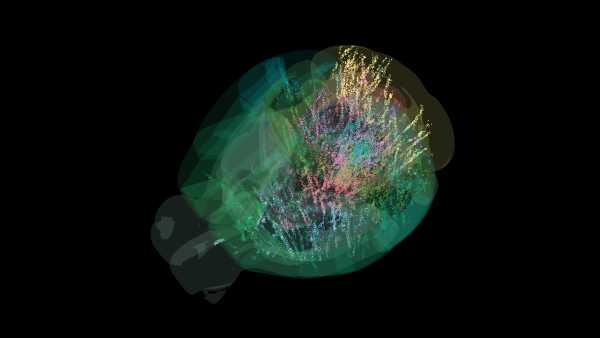

В іншому дослідженні, опублікованому раніше цього року в журналі iScience, вчені використовували добре відому модель хвороби Альцгеймера (ХА) на мишах. При ХА нейрони функціонують неправильно та з часом відмирають, частково через накопичення аномальних білків, включаючи амілоїд і тау-біотик. В експерименті одна група мишей добровільно бігала на колесах протягом шести місяців, тоді як інша група була малорухливою; активні миші показали менше накопичення амілоїду в корі головного мозку та кращий метаболізм і пам'ять, ніж їхні аналоги.

В іншій частині цього дослідження дослідники давали везикули мишей, які щойно займалися спортом, тваринам з малорухливою моделлю хвороби Альцгеймера. Вони виявили, що везикули, що вводилися через ніс, відтворювали метаболічні переваги, але не покращували пам'ять і не знижували рівень амілоїду.

Марк Феббрайо, професор Університету Монаша та член дослідницької групи, пояснив, що метод інтраназального введення міг вплинути на показники пам'яті, оскільки він вимагає легкої анестезії. Він повідомив Live Science в електронному листі, що його група зараз проводить подальші експерименти з учасниками-людьми, порівнюючи везикули, що прямують до мозку та з нього під час фізичних вправ. Попередні результати свідчать про те, що везикули, що прямують до мозку, можуть бути збагачені білками, що впливають на когнітивні функції.